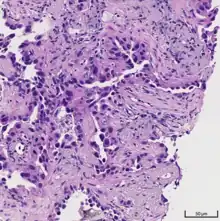

Histopathology

If possible, a biopsy of any suspected lung tumor is performed in order to make a microscopic evaluation of the cells involved and is ultimately required to confirm diagnosis.[7] Biopsy should be attempted in distant lesions first to establish a histologic diagnosis and to simultaneously confirm metastatic staging. The biopsy material is also used to analyze whether the tumor express any specific mutations suitable for tageted therapy (e.g. EGFR mutation or ALK mutation). Biopsy can be accomplished via bronchoscopy, transthoracic needle biopsy, and video-assisted thorascopic surgery (VATS).[4]

While sputum cytology has been shown to have limited utility, thoracentesis, or aspiration of pleural fluid with an ultrasound-guided needle, should be performed when pleural effusion is present. When malignant cells are identified in the pleural aspirate of patients highly suspect for lung cancer, a definitive diagnosis and staging (stage IV adenocarcinoma of the lung) is established.[4]

Adenocarcinoma of the lung tends to stain mucin positive as it is derived from the mucus-producing glands of the lungs. Similar to other adenocarcinoma, if this tumor is well differentiated (low grade) it will resemble the normal glandular structure. Poorly differentiated adenocarcinoma will not resemble the normal glands (high grade) and will be detected by seeing that they stain positive for mucin (which the glands produce). Adenocarcinoma can also be distinguished by staining for TTF-1, a cell marker for adenocarcinoma.[29]

As discussed previously, the category of adenocarcinoma includes are range of subtypes, and any one tumor tends to be heterogeneous in composition. Several major subtypes are currently recognized by the World Health Organization (WHO)[1] and the International Association for the Study of Lung Cancer (IASLC) / American Thoracic Society (ATS) / European Respiratory Society (ERS):[30][31][32] lepidic predominant adenocarcinoma, acinar predominant adenocarcinoma, papillary predominant adenocarcinoma, micropapillary predominant adenocarcinoma, solid predominant adenocarcinoma, and solid predominant with mucin production. In as many as 80% of these tumors, components of more than one subtype will be recognized. Surgically resected tumors should be classified by comprehensive histological subtyping, describing patterns of involvement in increments of 5%. The predominant histologic subtype is then used to classify the tumor overall.[2] The predominant subtype is prognostic for survival after complete resection.[33]

To reveal the adenocarcinomatous lineage of the solid variant, demonstration of intracellular mucin production may be performed. Foci of squamous metaplasia and dysplasia may be present in the epithelium proximal to adenocarcinomas, but these are not the precursor lesions for this tumor. Rather, the precursor of peripheral adenocarcinomas has been termed atypical adenomatous hyperplasia (AAH).[10] Microscopically, AAH is a well-demarcated focus of epithelial proliferation, containing cuboidal to low-columnar cells resembling club cells or type II pneumocytes.[10] These demonstrate various degrees of cytologic atypia, including hyperchromasia, pleomorphism, prominent nucleoli.[10] However, the atypia is not to the extent as seen in frank adenocarcinomas.[10] Lesions of AAH are monoclonal, and they share many of the molecular aberrations (like KRAS mutations) that are associated with adenocarcinomas.[10]